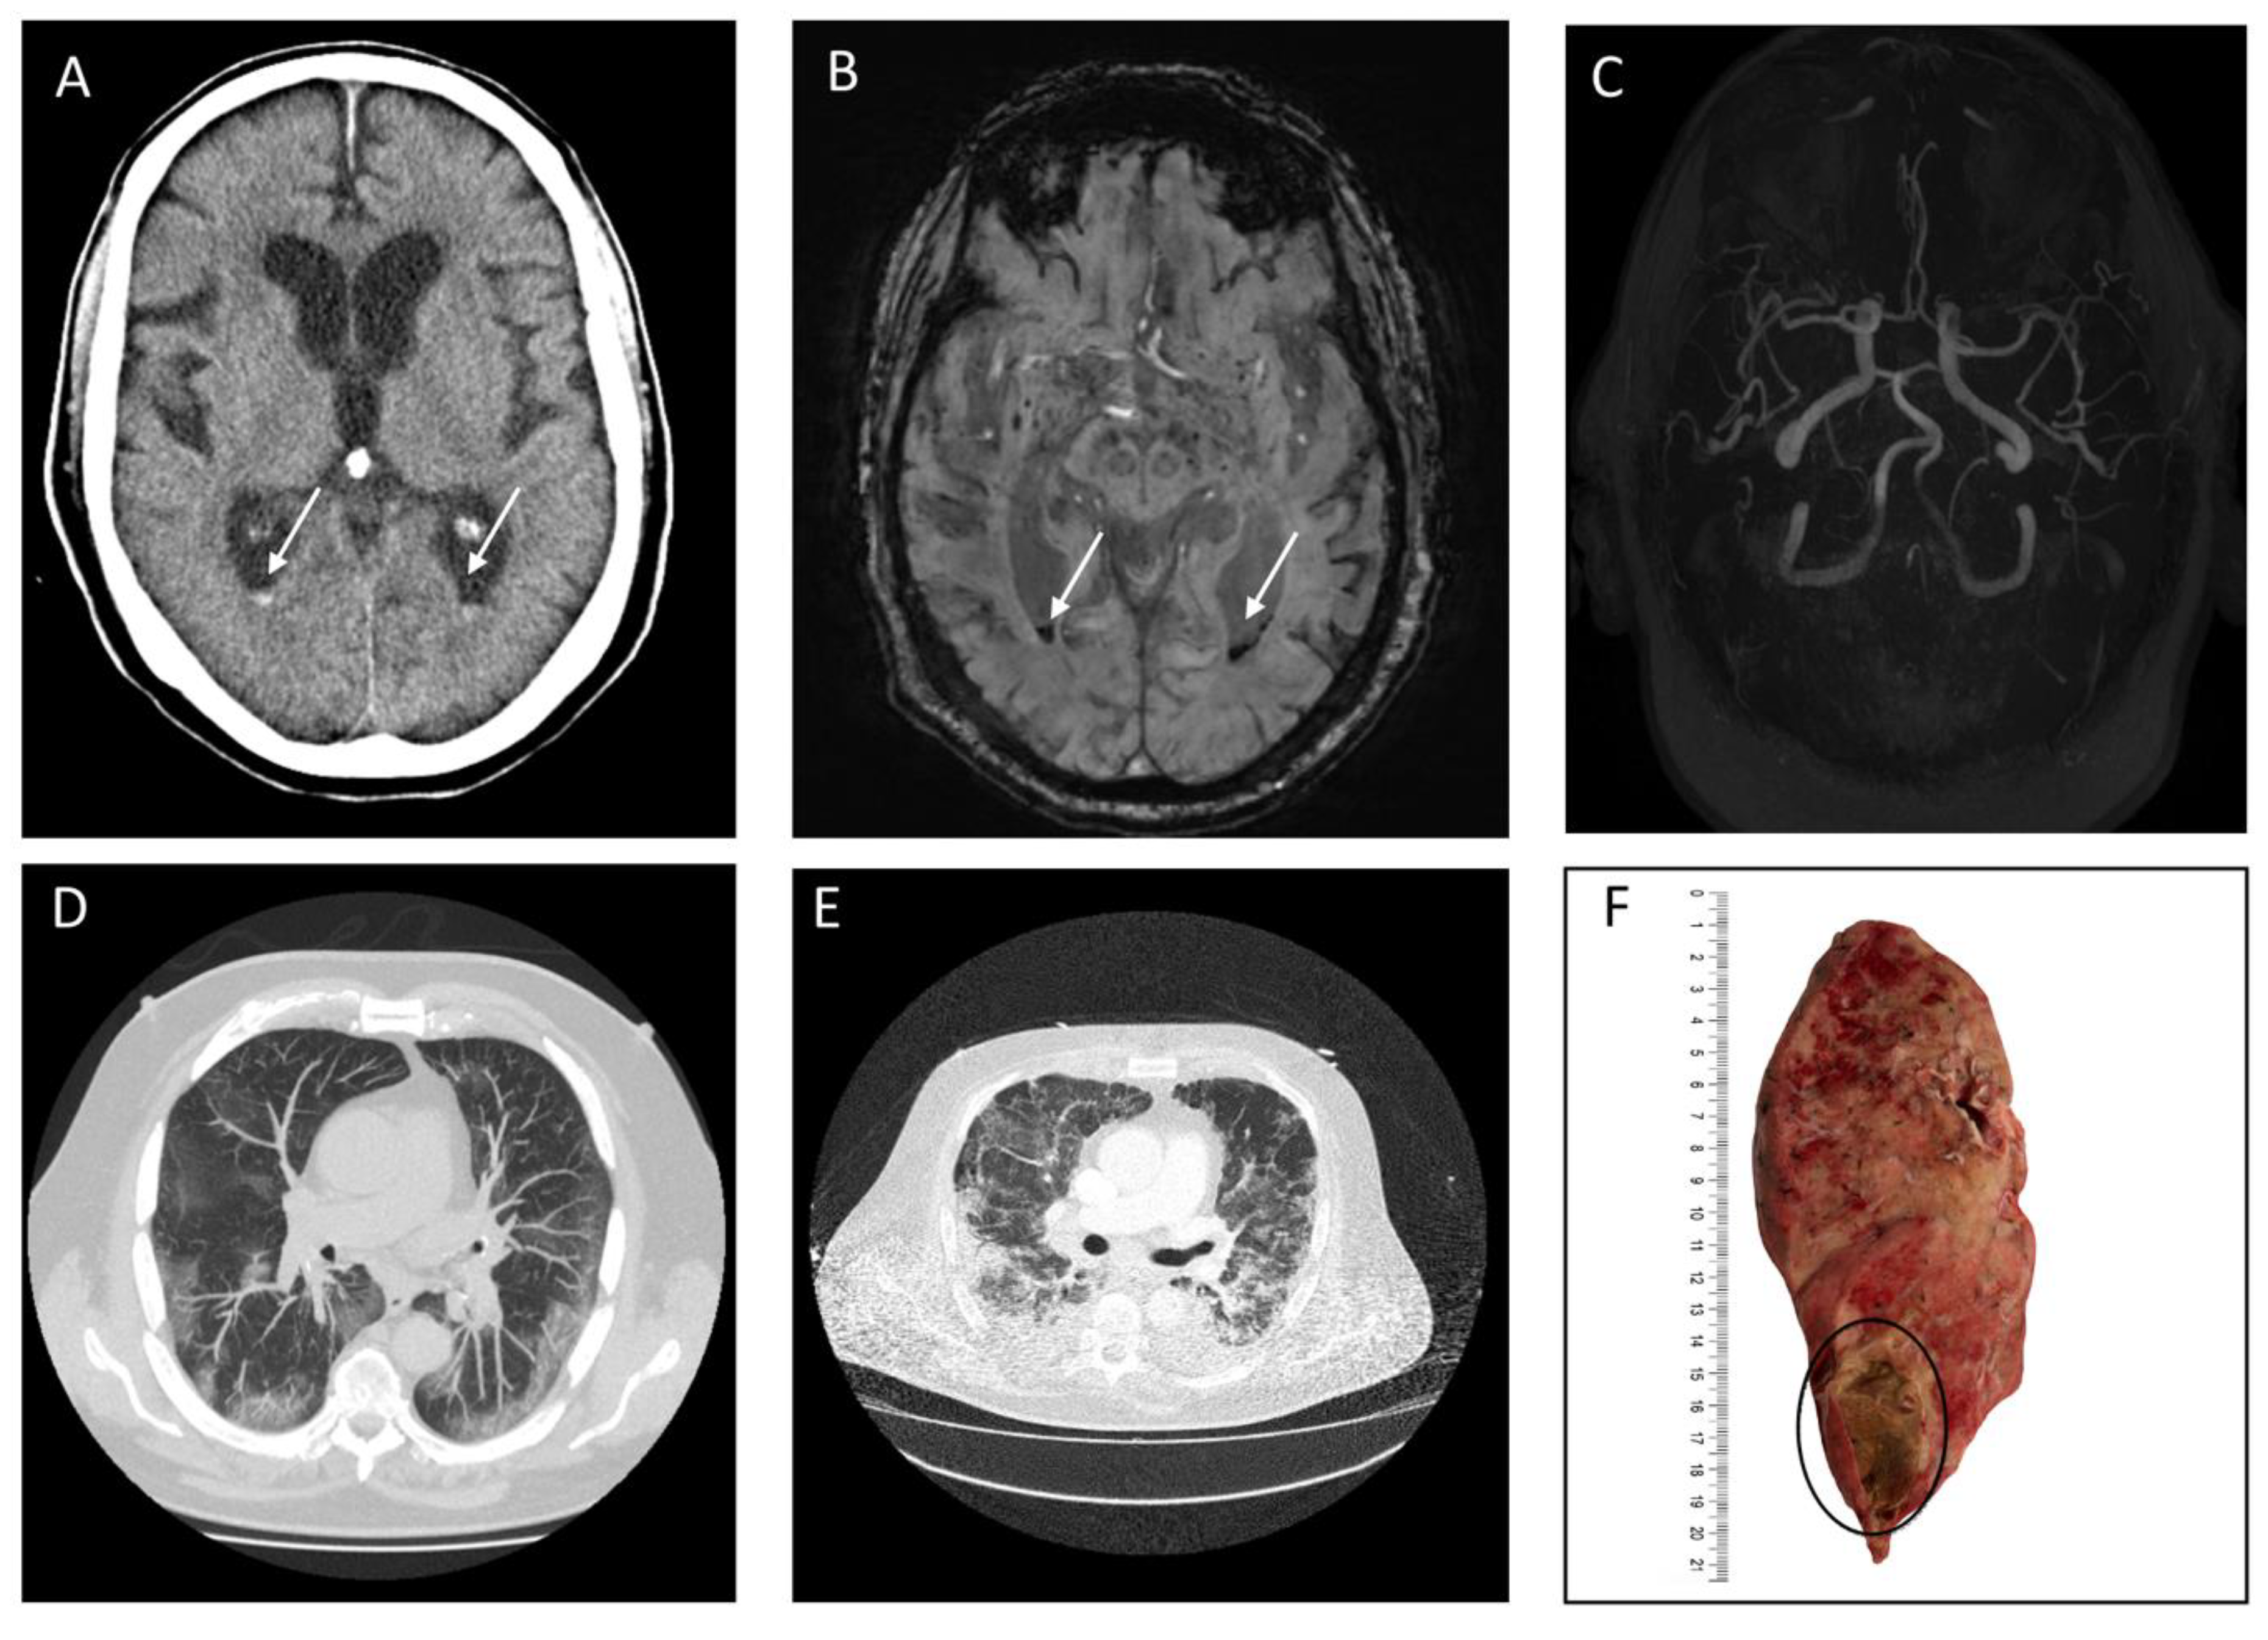

3.2. Imaging and Clinical Findings